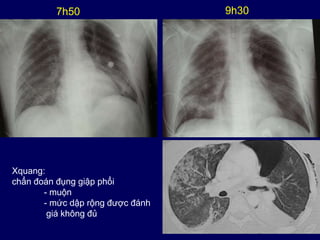

7h50 9h30

Xquang:

chẩn đoán đụng giập phổi

- muộn

- mức dập rộng được đánh

giá không đủ

Chẩn đoán đụng giập phổi:

Xquang so với CT scan ngực

• Trước 24 giờ, khoảng 50% đụng giập phổi của bệnh

nhân không được chẩn đoán bằng Xquang

(Pape HC, J Trauma. 2000 )

• Đụng giập phổi thực nghiệm

– Xquang ban đầu: không thấy 2/3 các đụng giập phổi

– CT scan ban đầu: 100% các đụng giập phổi

(Schild HH, J Comp Assisted Tomogr, 1989)